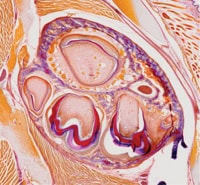

Diagnostic images can be shared the world over with tele-pathology systems